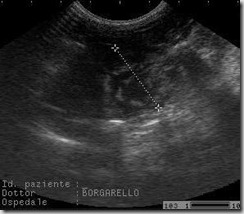

ECOGRAFIA

Il liquido pleurico appare di solito come uno spazio anecogeno o ipoecogeno tra la parete toracica o il diaframma e il polmone. L'esame ecografico oltre a confermare il versamento pleurico, è utile per la diagnosi di neoplasie polmonari, mediastiniche e pleuriche.

L'ecografia può essere usata per guidare l'inserimento preciso dell'ago nell'aspirazione ad ago sottile o nelle biopsie di masse pleuriche, mediastiniche e polmonari.